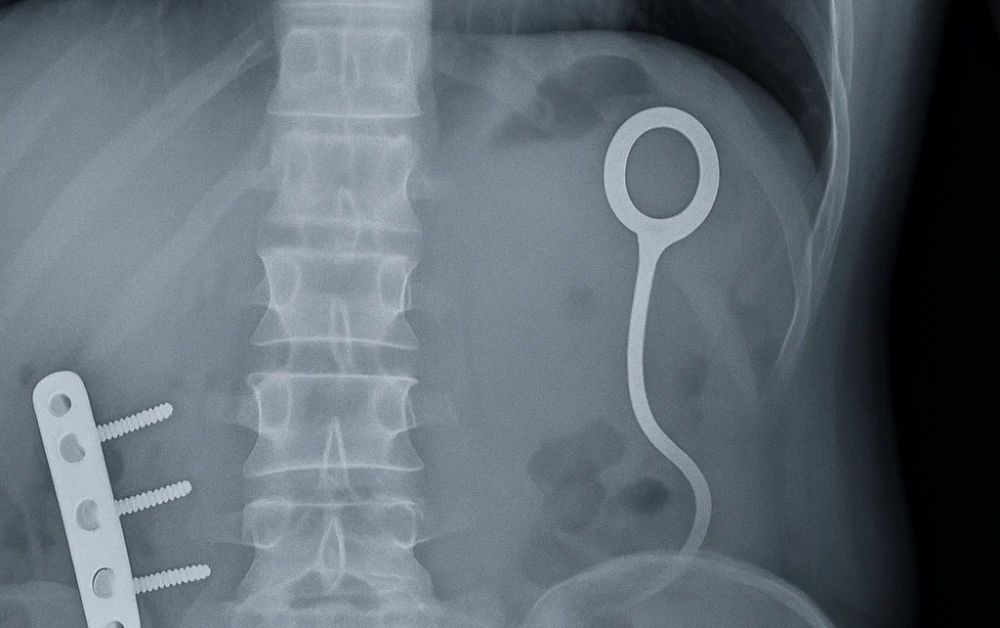

Portable X-ray systems are compact, mobile imaging systems designed to produce high-quality radiographs of patients who are unable to visit conventional X-ray rooms. These include portable X-ray generators, digital detectors, and connected software ,all in a highly mobile format that can be quickly moved on-site to any field within the hospital system – or beyond.

3. Compact Fluoroscopy Units

These dedicated portable units enable real-time imaging of:

• Interventional procedures in operating rooms

• Pain management injections

• Cardiac catheterization procedures

• Gastrointestinal examinations